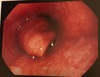

Esôfago

Fino pontilhado exsudativo brancacento sobre mucosa espessada Esofagite eosinofilica